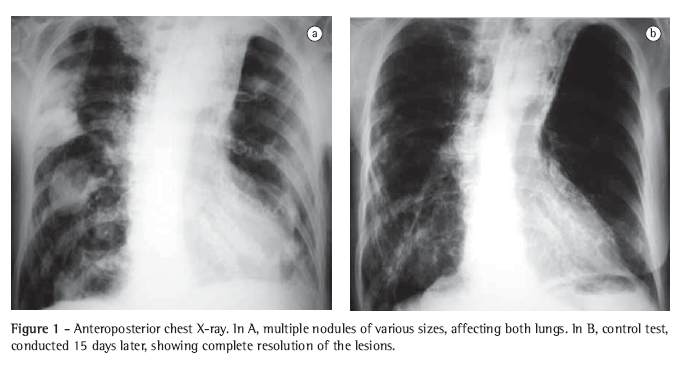

A computed tomography (CT) scan of the chest revealed nodules, some cavitated, of various sizes (Figure 2). Three sequential sputum samples were tested for acid-fast bacilli and fungi (silver staining), and the results were negative. In the three sputum samples collected, smear microscopy (Gram staining) revealed filamentous bacteria, strongly suggestive of Nocardia spp., which was confirmed by Ziehl‑Neelsen staining, showing the characteristic partial acid-fastness (Figure 3).

The chest X-ray presentation of pulmonary nocardiosis is nonspecific. The most common radiological findings are consolidations and large irregular nodules. Nodules, cavitated masses, pleural effusion, pneumothorax, ground-glass opacities and interstitial patterns can occur as well.(1,4,5,11) Some studies show that, in HIV-infected patients, there is a higher percentage of cavitated lesions.(8) Alveolar consolidation in the upper lobes is often confused with pulmonary tuberculosis.(6) Although the alterations observed on CT scans are similar to those of the conventional X-rays, CT is superior in demonstrating the exact location and extent of the lesions, as well as in the differentiation between pulmonary and pleural lesions.(5) In the case reported, the patient presented nodules of various sizes, disseminated throughout both lungs, and some of those nodules were cavitated.